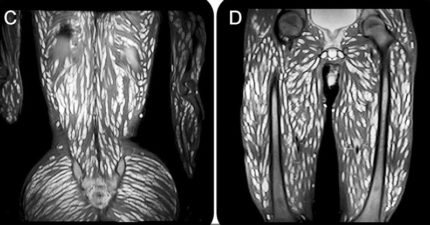

男子「感官扭曲」站不下去 檢查發現「全身爬滿蟲」畫面超驚悚!